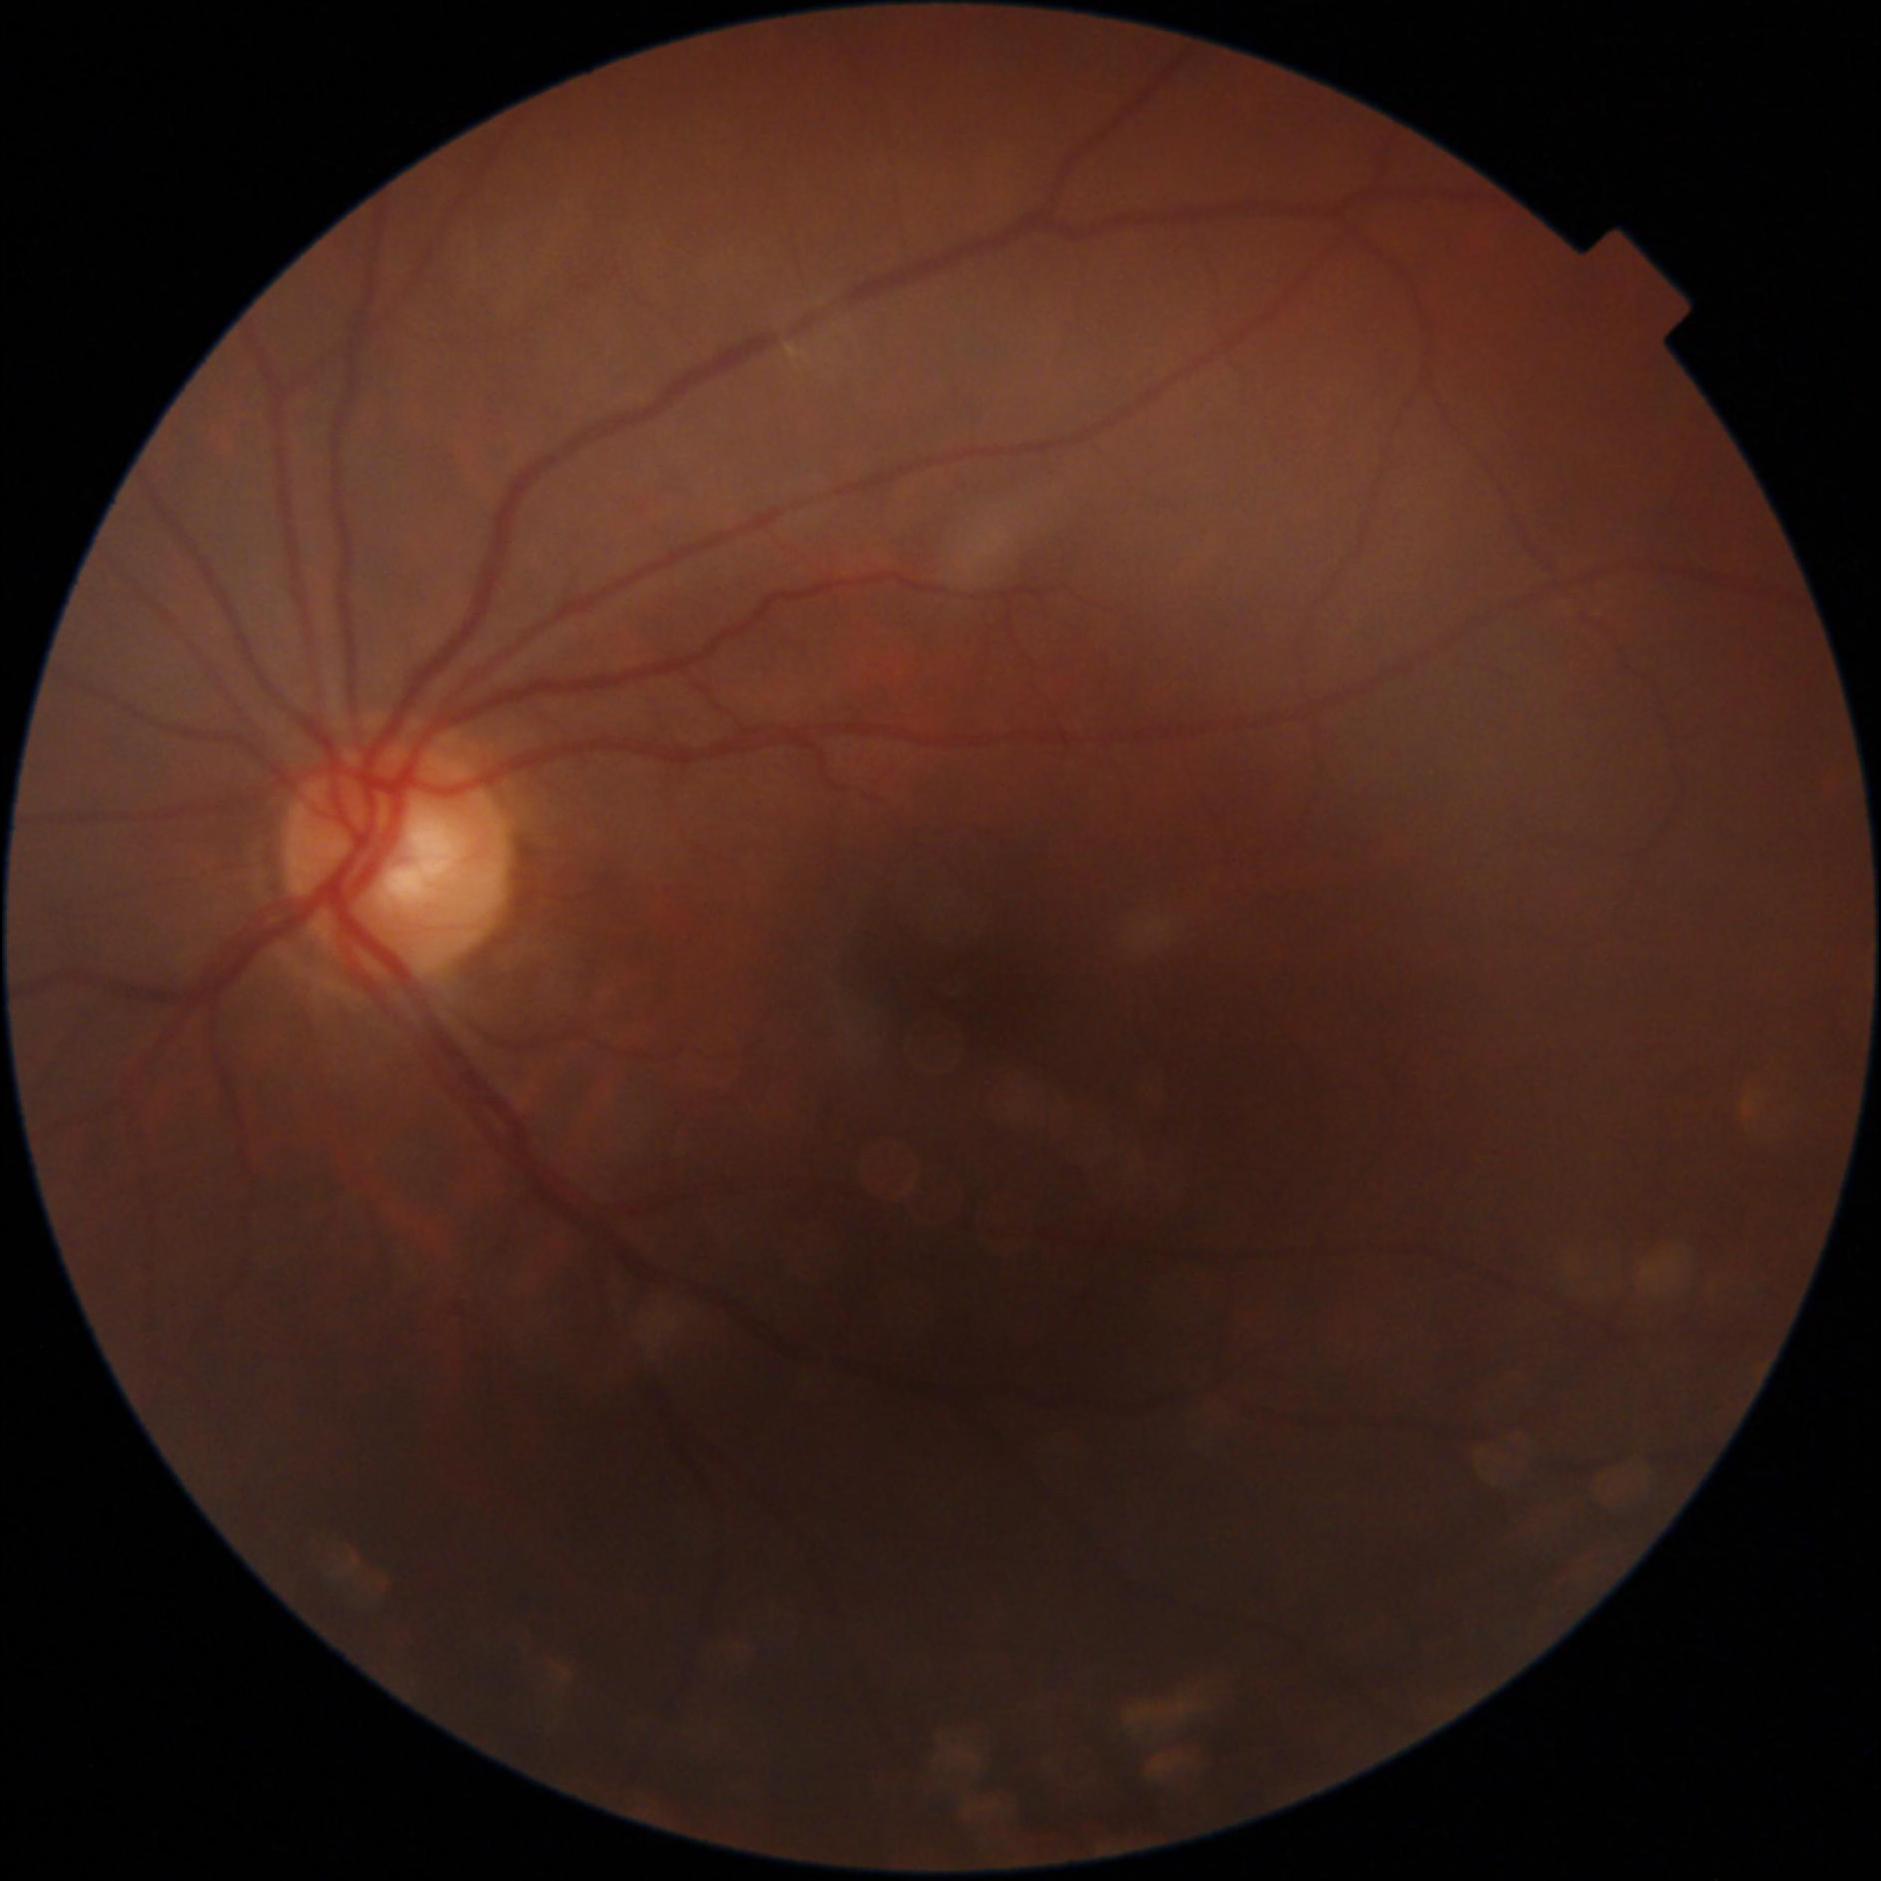

GON is diagnosed through a comprehensive ophthalmic examination that includes intra-ocular pressure (IOP) measurement, anterior chamber and angle assessment, optic disc (OD) inspection, visual field assessment, and optic nerve head imaging [1, 4]. Although effective, these procedures require the expertise of an ophthalmologist and access to specialized, often costly, equipment, which can be a limiting factor. Alternatively, computer-aided analysis of digital fundus images (DFI) can be used to identify GON. DFIs are captured using a fundus camera, which photographs the posterior segment of the eye and provides a clear view of the OD [5].

Recent studies have increasingly utilized deep learning (DL) models for automated GON detection using DFIs [6–8]. However, a major limitation in published research is that GON reference labels are often derived solely from DFI evaluations rather than comprehensive ophthalmic examinations [9–12]. This approach intrinsically reduces the GON detection task to a subjective evaluation of the OD, which has inherent limitations in identifying GON. Consequently, DL models trained exclusively on DFIs may inherit biases, be influenced by subjective interpretations, and inconsistent annotations, include examples that are not verified and potentially diverge from the true clinical manifestation of GON. Additionally, this method can be error prone, since other ophthalmic conditions may mimic the appearance of a GON cupped optic disc, such as ischemic optic neuropathy and compressive optic neuropathy [13].

The dataset was curated by the Hillel Yaffe Ophthalmology Department Glaucoma Unit, Hadera, Israel, between 2022-2024. DFIs were captured using a TOPCON DRI OCT Triton retinal camera with a 45° FOV. The dataset includes subjects aged 36 to 95 years, with 73% of the DFIs classified as glaucomatous. Patient selection followed specific inclusion and exclusion criteria to ensure data quality and clinical relevance.

All DFIs were deidentified, ensuring that any personal identifiers were removed. To maintain consistency, images were cropped to a square format by removing black borders. A quality score for each DFI was computed using FundusQ-Net [5] and is included in the dataset.

The dataset consists of 747 DFIs, including:

- 548 glaucomatous DFIs (73%)

- 199 non-glaucomatous DFIs (27%)